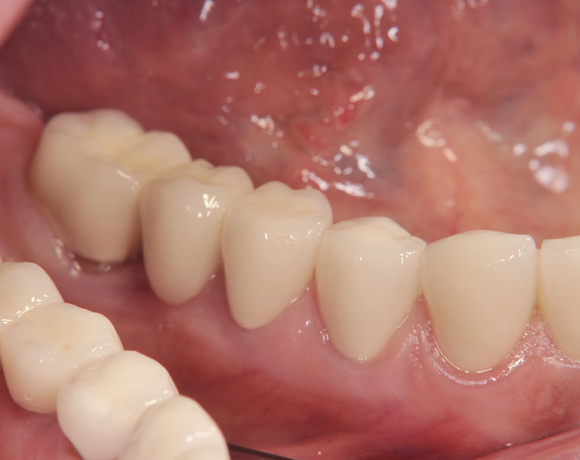

Der vorliegende Patientenfall zeigt eine komplette Neuversorgung der vorhandenen Metallkeramikkronen mit vollkeramischen Restaurationen. Zusätzlich wurde im Oberkiefer die Zahnreihe mit zwei Implantaten, für die fehlenden Molaren, ergänzt. Da keine ausreichende Knochenhöhe vorhanden war wurde ein interner Sinuslift geplant.